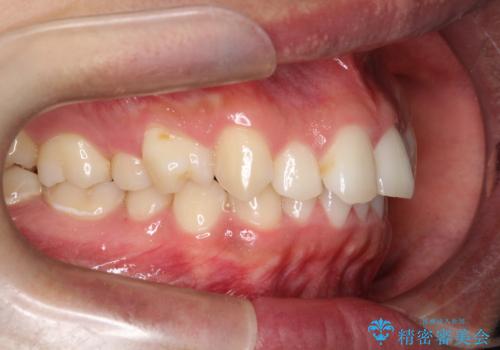

治療途中では咬み合わせの改善を目的としてバイトアップを行い、歯の捻転や叢生を改善しつつ、機能的に安定した咬合を獲得しています。

治療期間は3年2ヵ月と比較的長期となりましたが、見た目の歯並びだけでなく、咬み合わせまでしっかり整えた症例です。

上顎左右4番は90度捻転していたため、改善後歯根露出してしまっているためCTG(歯肉移植)を行う予定です。